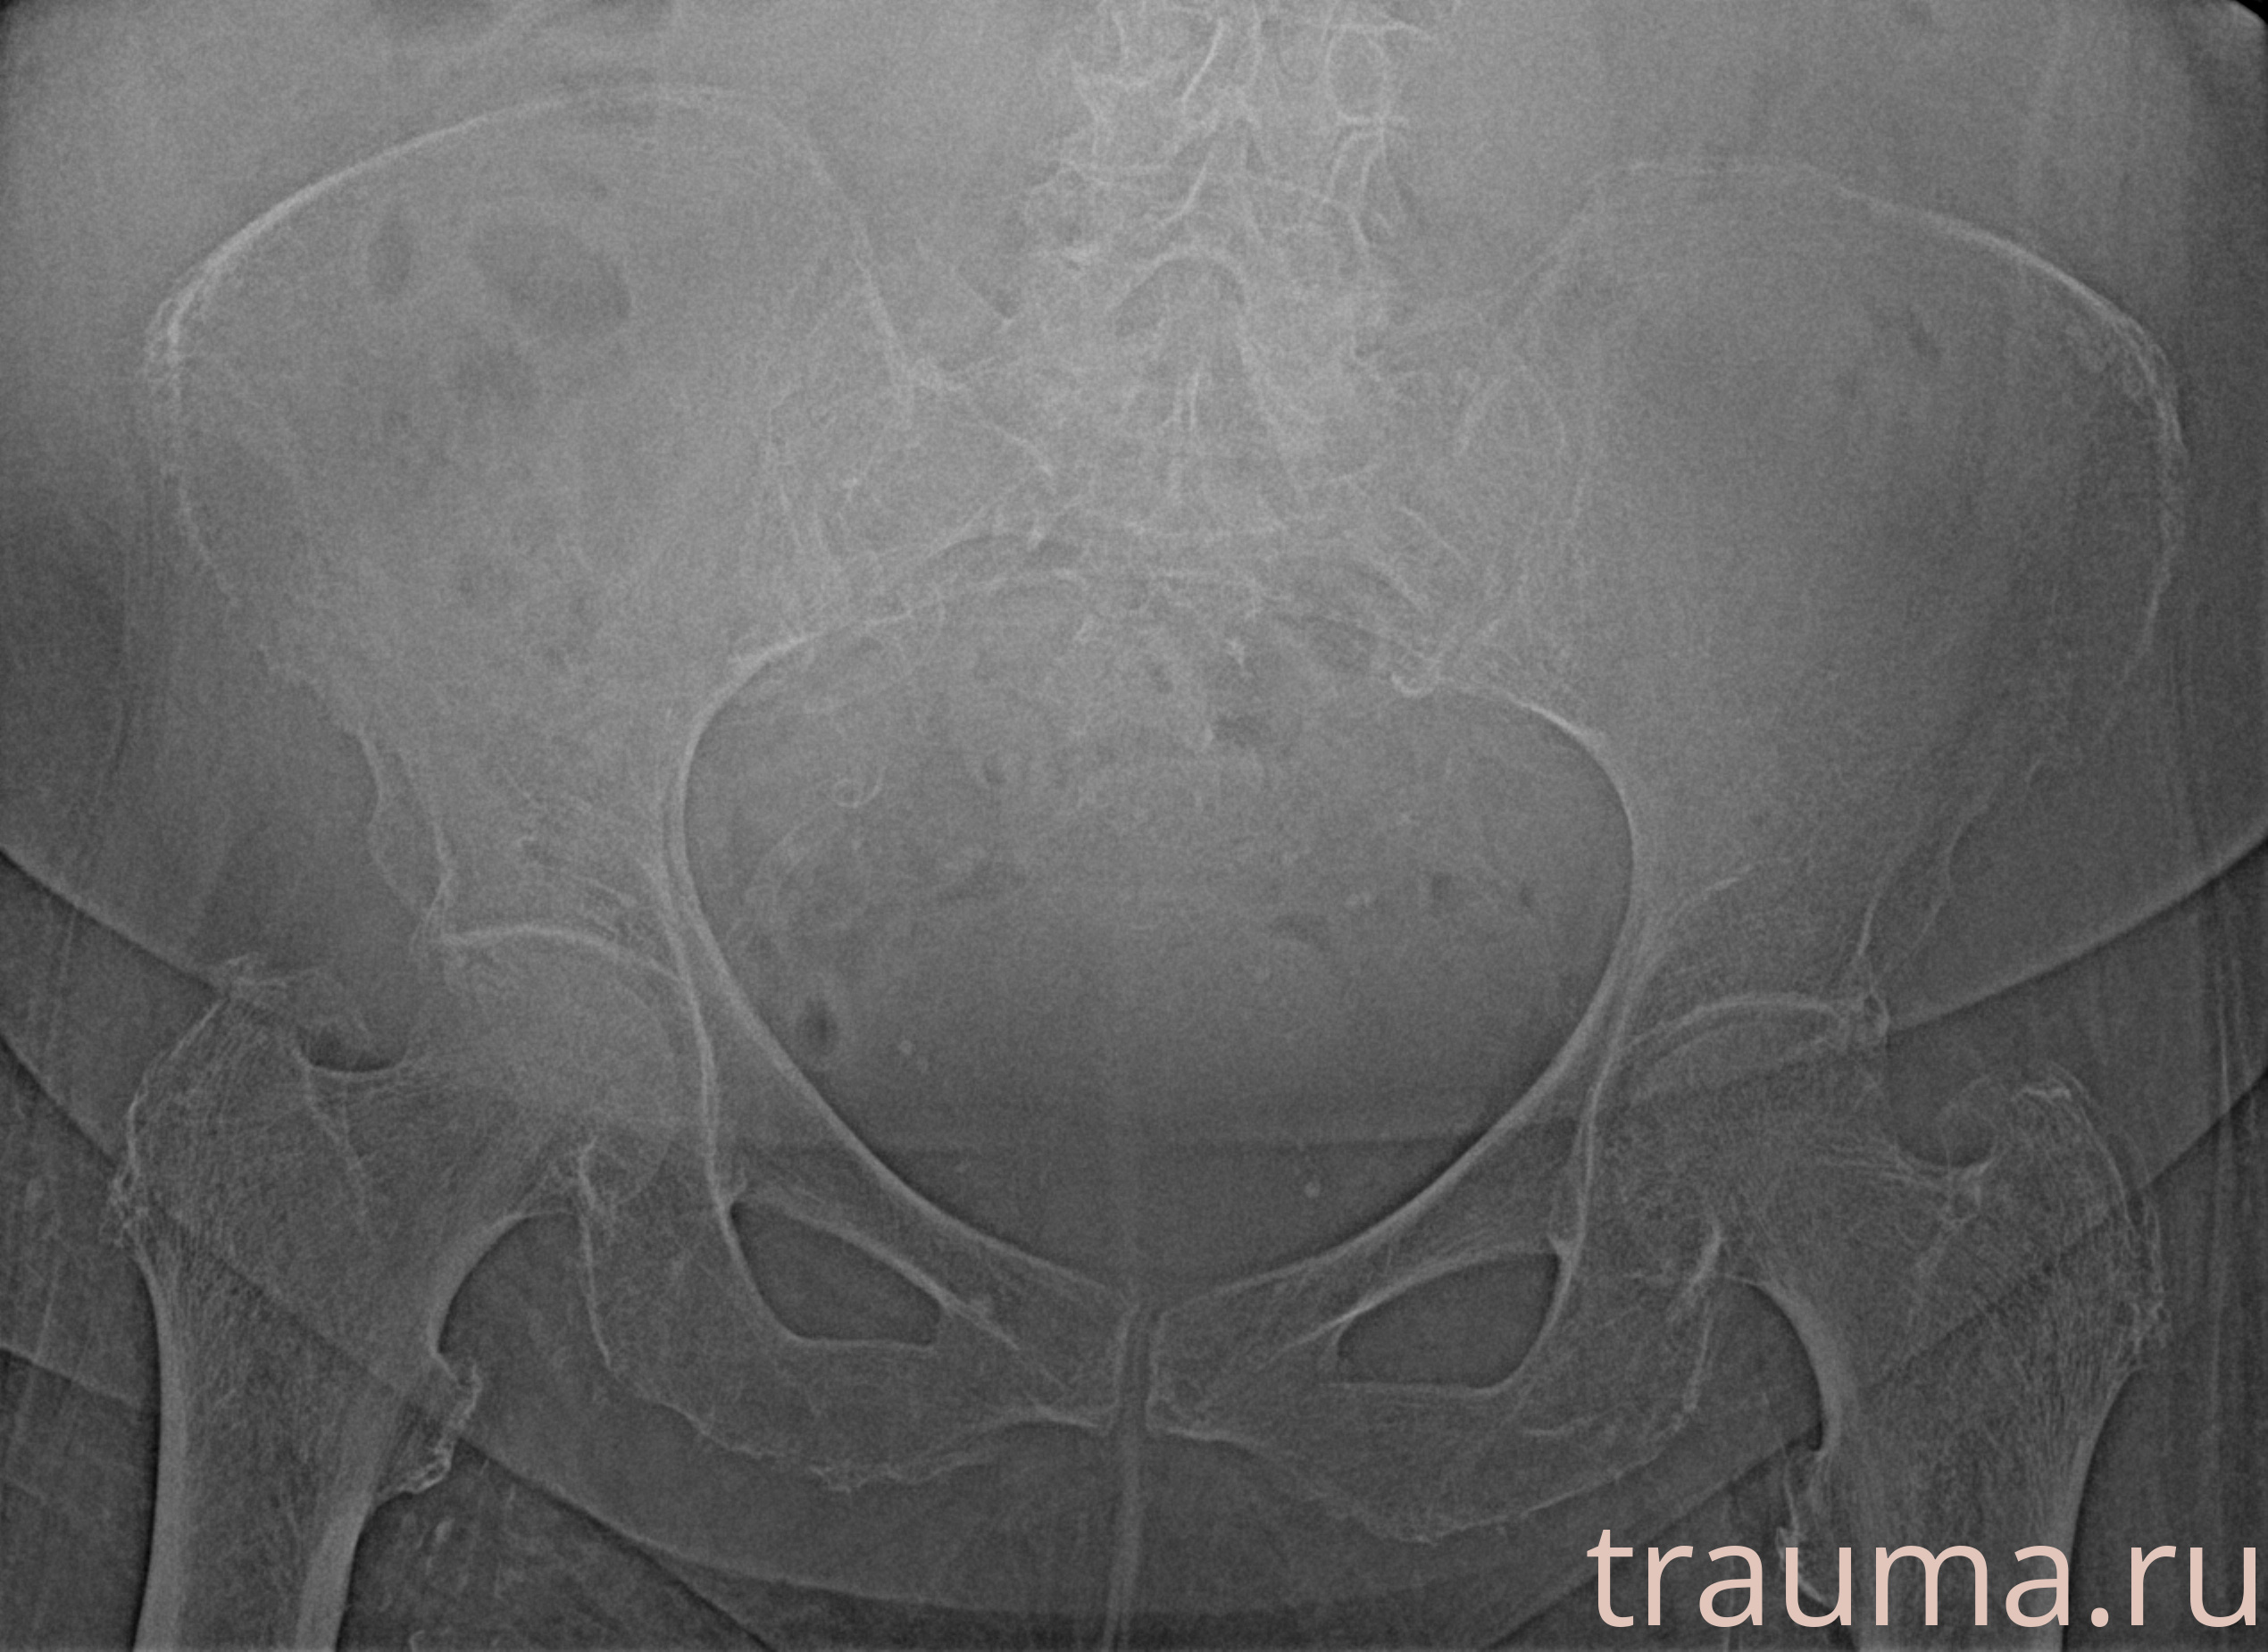

Рентген на дому: по вашему адресу приезжает врач-рентгенолог, травматолог-ортопед с мобильным рентгеновским аппаратом, проводит диагностику травмы или заболевания, делает необходимые рентгенограммы, дает рекомендации по дальнейшему лечению. Получить качественные снимки в домашних условиях возможно благодаря уникальной методике, разработанной МосРентген Центром для института  Склифосовского